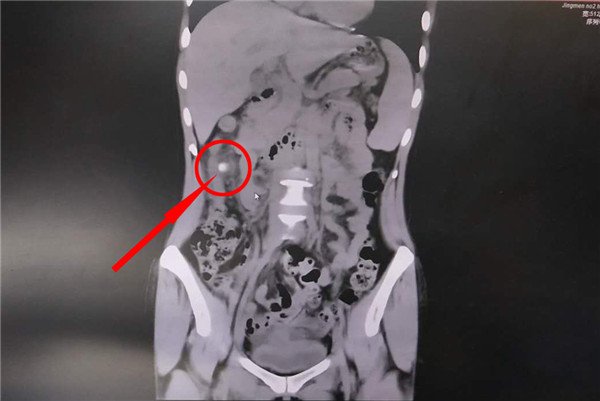

CT影像锁定“元凶”——憩室发炎肠穿孔

▲腹痛“元凶”——升结肠憩室伴粪石嵌顿

结合小林血常规指标(白细胞升高)、CT影像上升结肠旁的亮点(粪便在鼓包内形成的粪石)以及肠管壁增厚等因素,确诊为“结肠憩室伴粪石嵌顿”。“只有憩室发炎了才会引起腹痛等症状,炎症时间长了会形成肠壁溃疡,这个薄弱处就会引起肠穿孔和腹膜炎等严重并发症。”小林目前的情况极有可能是如此,但憩室炎和肠穿孔还需通过腹腔镜进一步探查。